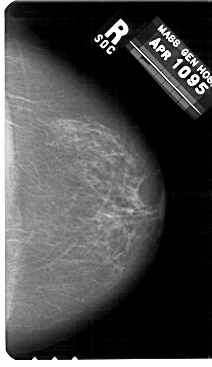

A_1479_1.RIGHT_MLO

RIGHT_MLO LINES 5416 PIXELS_PER_LINE 3316 BITS_PER_PIXEL 12 RESOLUTION 43.5 NON_OVERLAY